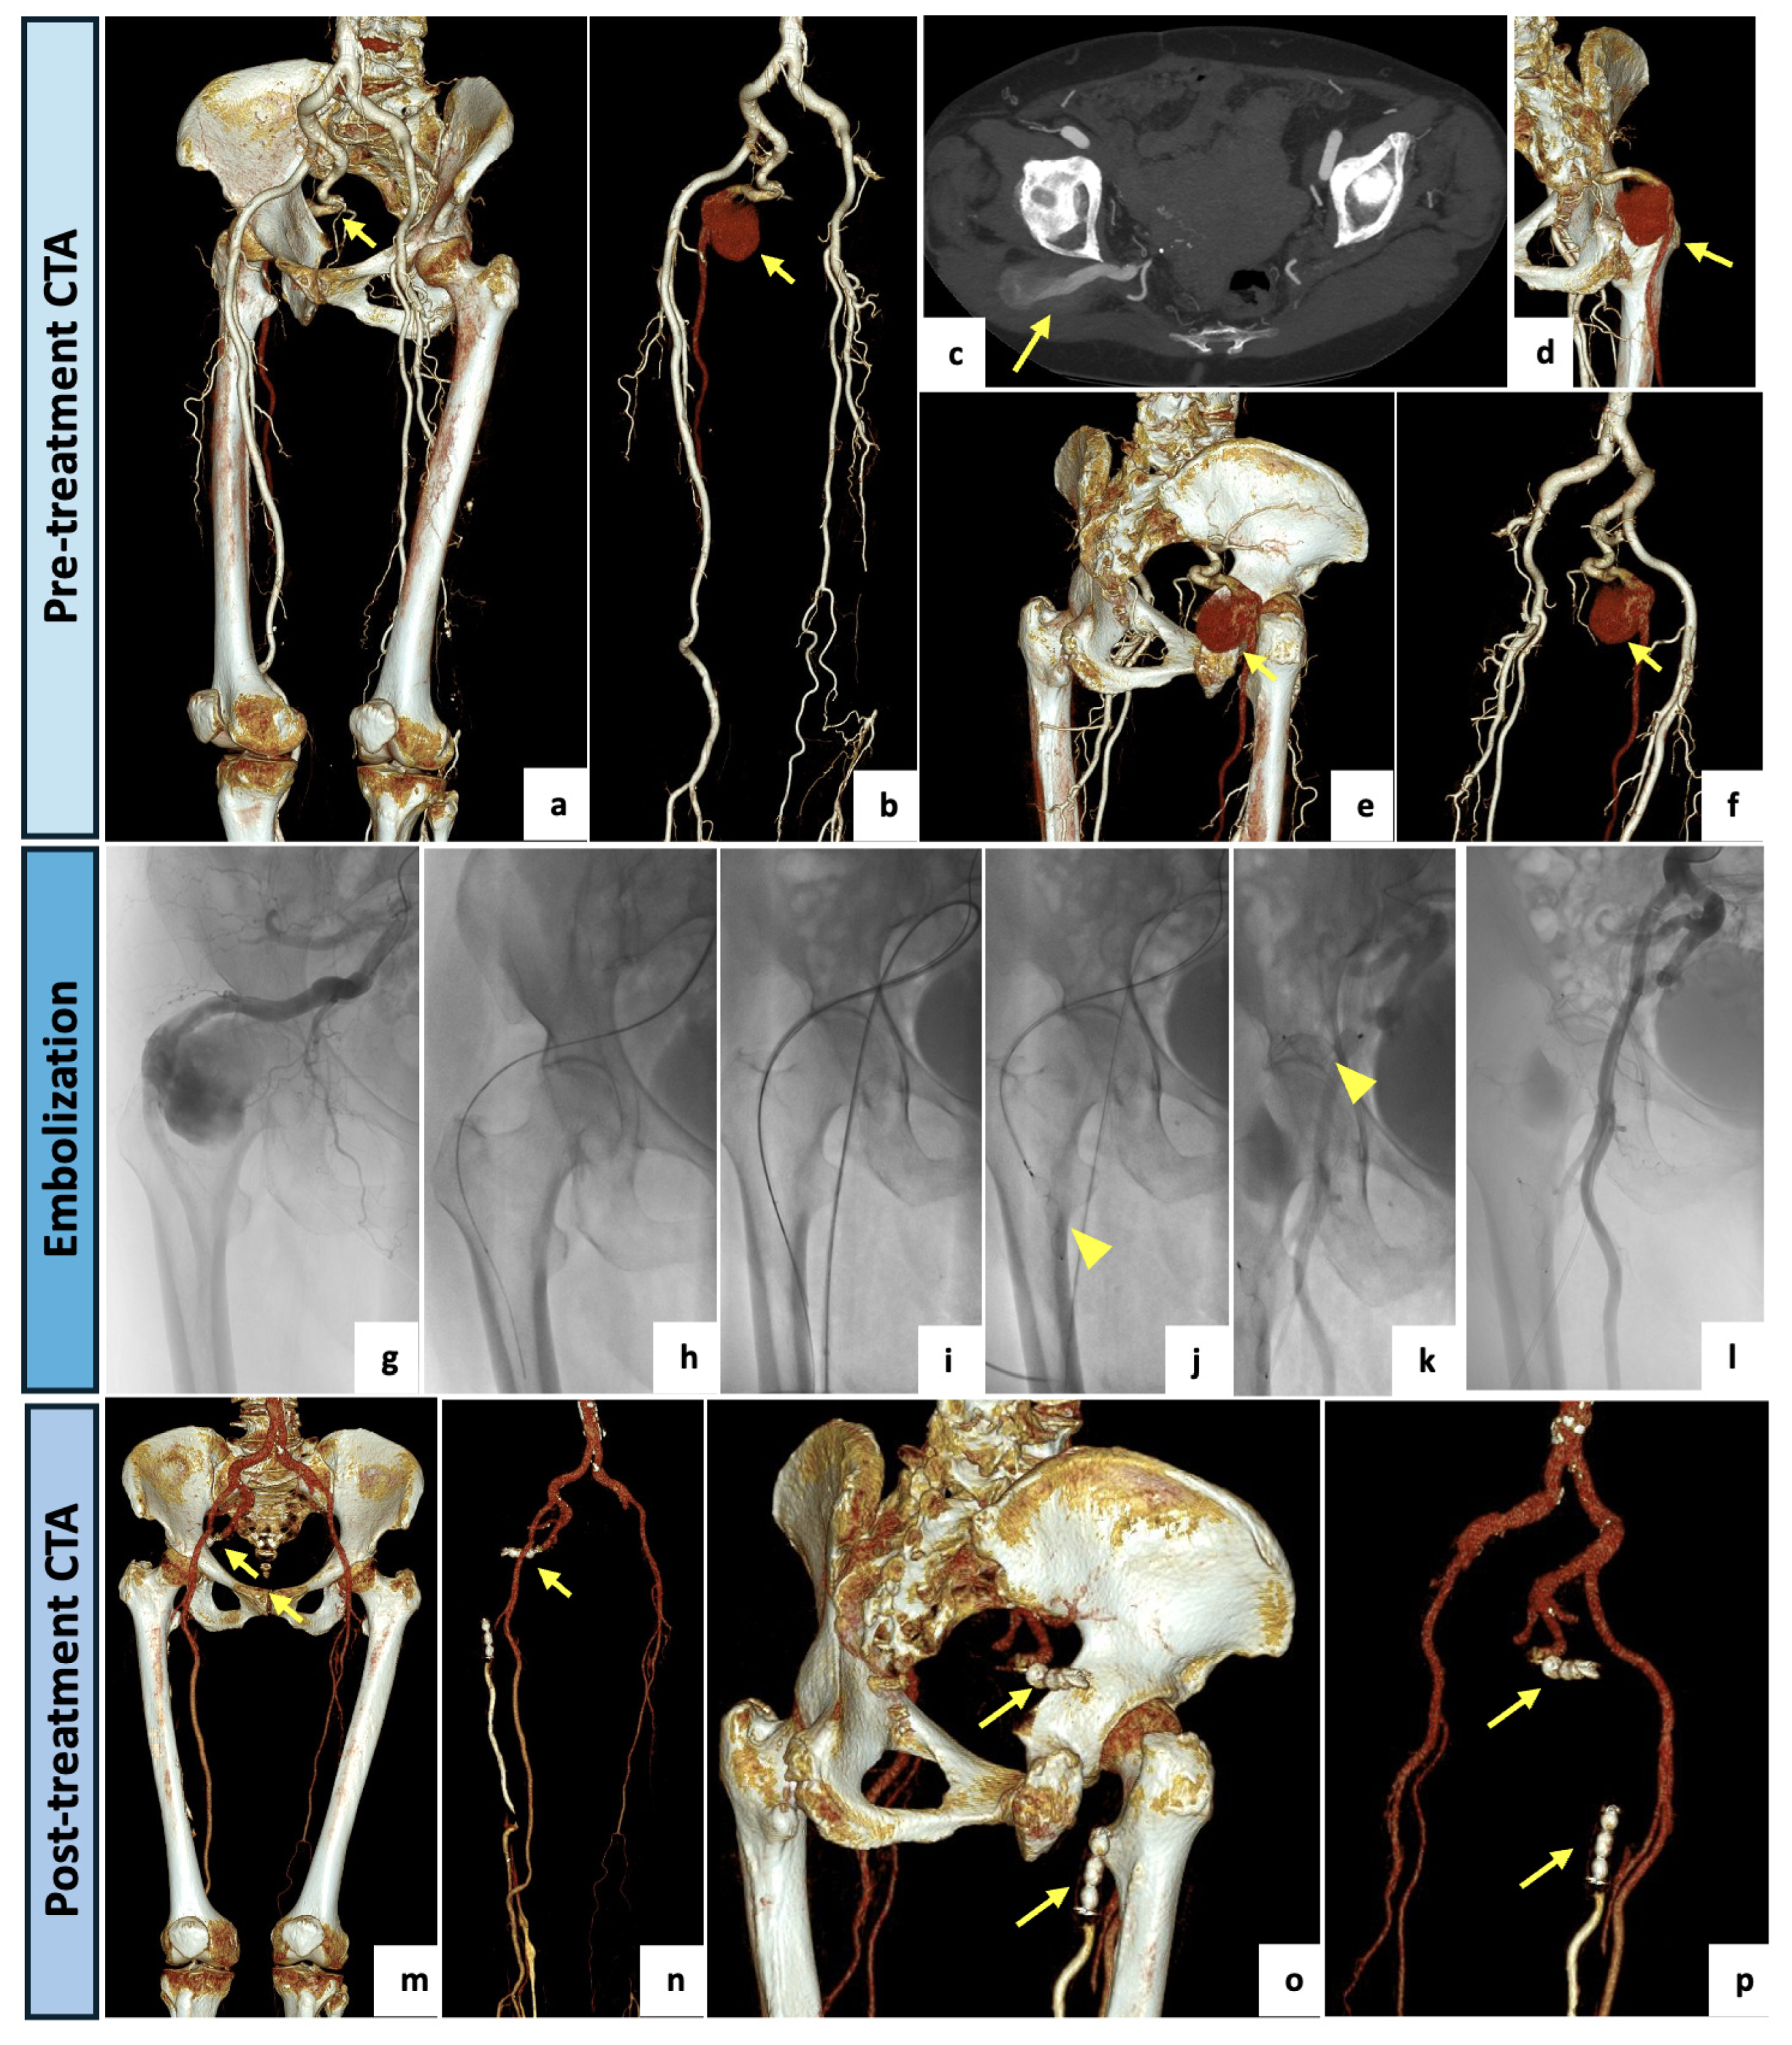

The next patient was a healthy 53-year-old male referred to the Vascular Surgery Department of our center for critical ischemia with rest pain of the right lower limb. Upon physical examination, stable vital signs, palpable and symmetric femoral pulses, absent right popliteal and pedal pulses and mild hypothermia of the right foot were detected. Neurological examination revealed no motor or sensory deficit. The CTA examination (Figure 3) showed a right aneurysmatic complete PSA (23 mm in the maximal caliber) with extensive luminal thrombus originating from the internal iliac artery. The right external iliac artery was hypoplastic, probably due to a steal syndrome caused by the PSA. The ipsilateral SFA appeared incomplete and noticeably reduced in caliber (type 2a). A thrombotic occlusion of the left popliteal artery and left tibio-peroneal trunk tibial axis with filling thrombotic defects at the anterior tibial artery were observed. The posterior tibial and peroneal arteries were patent. The case was collegially discussed, and a hybrid approach was preferred. Firstly, a right femoro-tibial bypass with the anterior tibial as the target artery was performed under general anesthesia using the ipsilateral great saphenous vein in a reversed fashion. After two days, the patient subsequently underwent endovascular embolization of the aneurysmal PSA. The procedure was performed in our angiographic suite. A left femoral access was obtained under local anesthesia. The sciatic artery was catheterized and embolized using a 12 mm Amplatzer Vascular Plug II (Abbott Medical, North Plymouth, MN, USA) deployed immediately distally to the internal pudendal artery origin. Both of the procedures were conducted without complications. At the 3-month CTA follow-up examination, the bypass was patent, and the aneurysm was completely excluded.

Figure 3.

(a,b) VR reconstruction of the preoperative CTA showing a right complete PSA originating from the internal iliac artery (arrow). The right external iliac artery appears hypoplasic and the SFA appears incomplete and diminished in caliber (type 2a). (c) Axial view showing an aneurysmal dilatation (23 mm) of the PSA with luminal thrombus (arrow). A hybrid approach was preferred, with the first step consisting of a left femoro-tibial bypass with the anterior tibial as the target artery. (d–f) Selective angiographic images preliminary to the endovascular step showing a patent femoro-tibial bypass. (g–j) After a contralateral 6F-sheat femoral access, the aneurysmal PSA was selectively catheterized and completely embolized using a 12 mm Amplatzer Vascular Plug II (arrowhead) deployed immediately distally to the internal pudendal artery origin. (k–n) VR reconstructions of the postoperative CTA (3-month) demonstrating the patent femoro-tibial bypass with complete exclusion of the aneurysmal PSA (arrows).